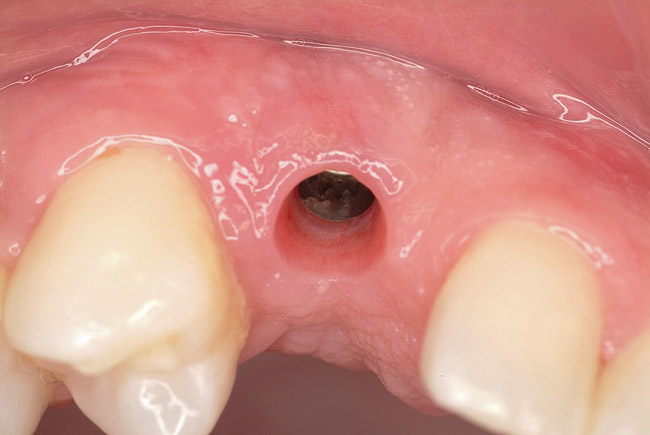

Figure 9  Primary stability of the implant achieved, facilitating a transmucosal healing approach.

Figure 9

Approximately 4 months after grafting, the patient returned for clinical and 3-D radiographic evaluation. The thinnest area of ridge width preoperatively was remeasured in approximately the same location, demonstrating a gain of about 4 mm (Figure 7). The treatment plan was to place a 3.5-mm x 13-mm implant with a computer-generated guide (SiCat, Sirona Dental, www.sironausa.com), eliminating an additional open surgical procedure. Planning included initial osteotomy preparation with single-use drills combined with a localized ridge expansion using narrow, tapered osteotomes. This was performed approximately 5 months after the augmentation procedure, achieving primary stability of the implant, facilitating a transmucosal healing approach (Figure 8 and Figure 9). Following each step of osteotomy preparation, a probe was inserted along the walls of the site to confirm the integrity of the buccal and palatal walls prior to implant insertion.

Ten weeks after implant insertion, the patient presented to begin soft-tissue contouring via a fixed, provisional crown (Figure 10). Deliberate under-contouring of the cervical portion of the temporary restoration was performed to avoid unwanted mucosal recession and possible esthetic complications (Figure 11 and Figure 12).